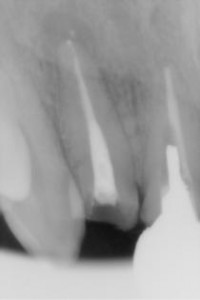

この患者さんは、この歯が痛くて来院されました。以前の根管治療もそこそこできているように見えますが、残念ながら痛みが出てきているので、根管治療をやり直すことにしました。最初に抗生剤と痛み止めを飲んでいただいて、痛みが落ち着いた後に根管治療をすることにしました。抗生剤がよく効いたせいか、根管治療にはやや不同意な感じにもなったのですが、このままかぶせを作ると何年かあとに必ずまたいたくなりますので、根管治療を行いました。

治療回数7回、約1ヵ月半で根管充填を行いました。(かなりスムースにいったつもりです、)この期間を長いと考えるか、短いと考えるかは考え方によります。 根管充填は垂直加圧充填法で行いました。向かって左の根管もきちんと掃除をしての充填です。